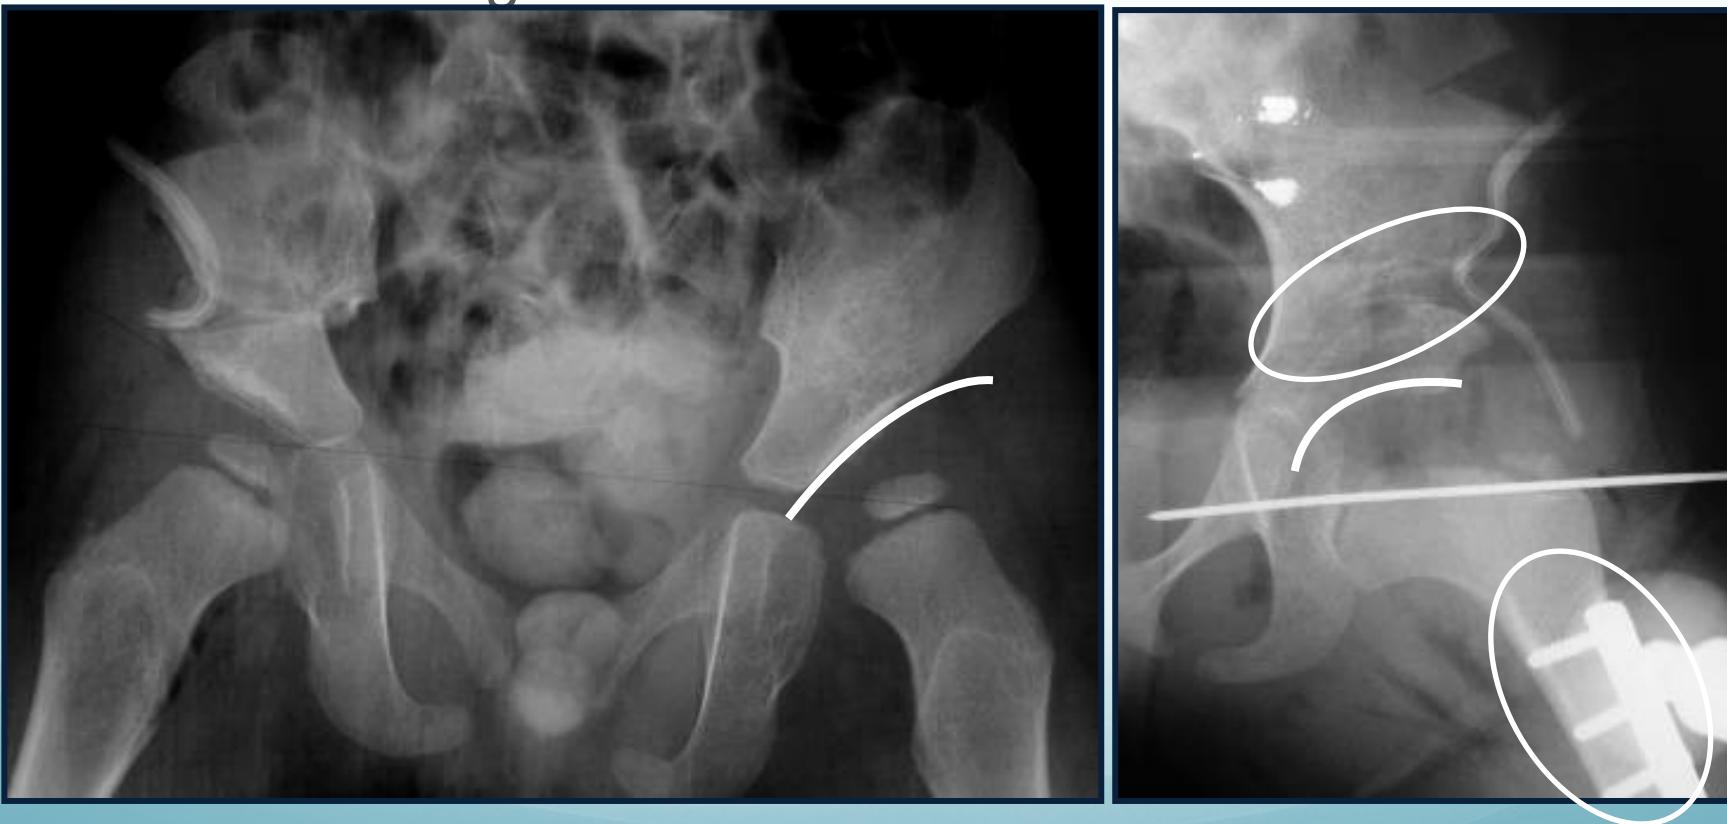

6-12 months of age

- Closed reduction & hip spica cast

- Arthrography-guided

12-24 months of age

- Surgery

- Open reduction & Acetabuloplasty (pelvic osteotomy)

Above 2 years of age

- Open reduction & Acetabuloplasty & Femoral shortening